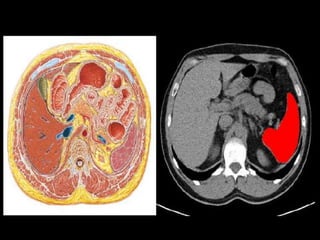

MRI anatomy images of the abdomen.

MRI anatomy imagesof the abdomen.